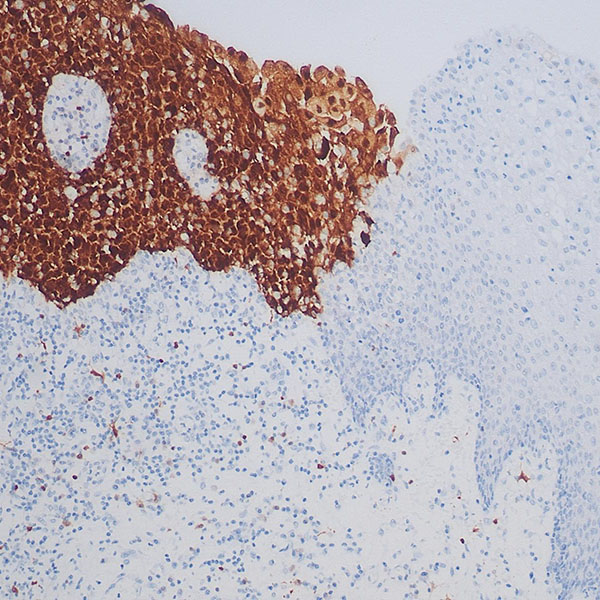

免疫组化染色

组织病理学实验